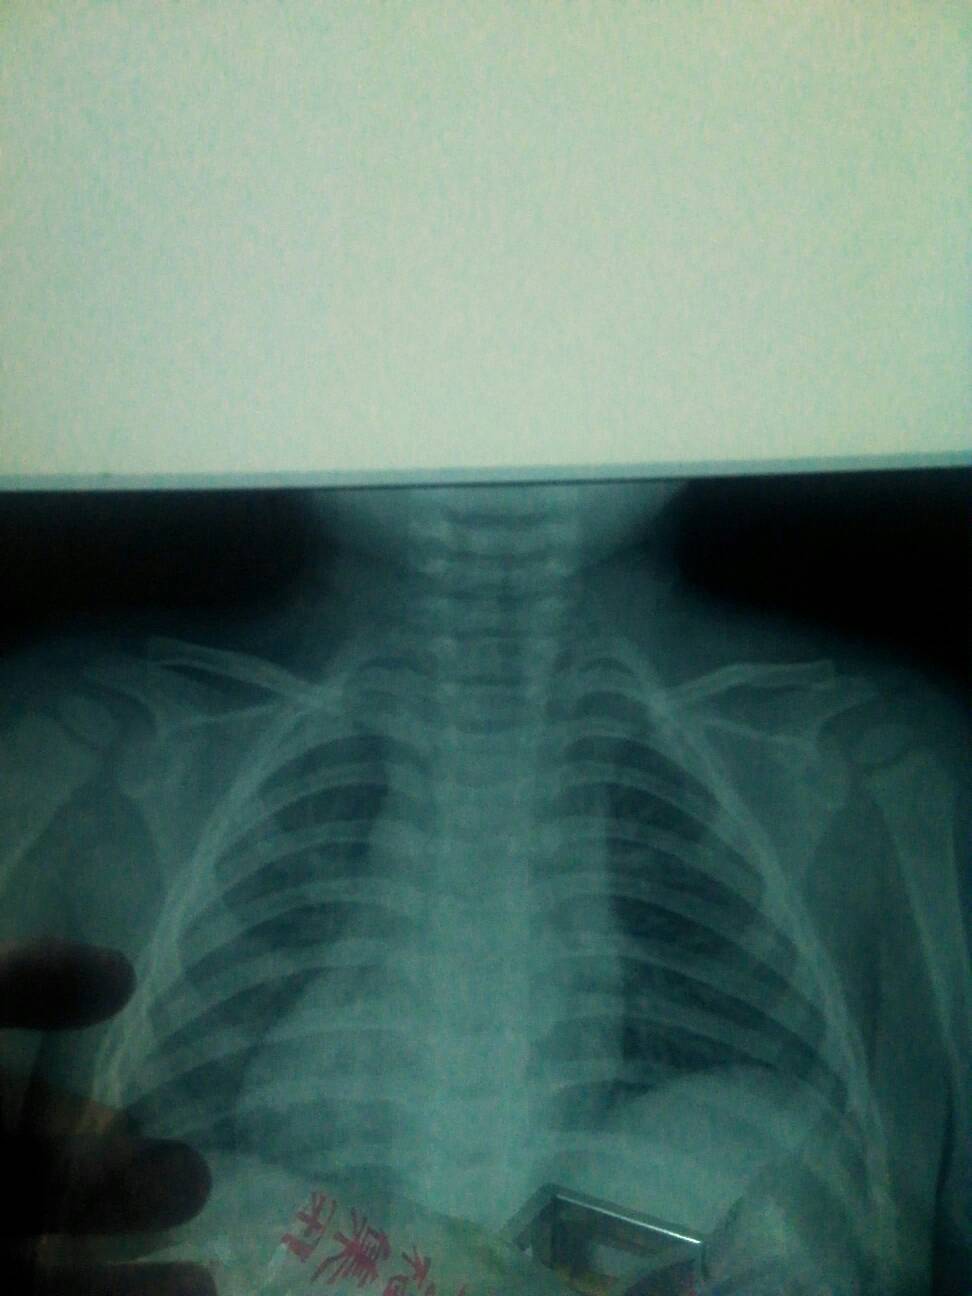

这个16岁宝宝锁骨骨折要不要紧? 点击展开 简简//单单 2015-05-01 20:41 为您推荐: 其他回答 你好,谢谢咨询,根据你的片子情况,看到骨折错位是比较明显的,加上孩子16岁,个人觉的单纯使用8字绷带悬吊效果不甚理想,建议你还是到进行手术治疗,是最好的选择的。 圣手仁心windy 2015-05-01 22:03 相关问题 宝宝锁骨骨折不绑东西要紧吗 锁骨骨折能不能吃牛肚 宝宝锁骨骨折,肩膀感觉一高一低,不平衡,该怎么办呢?